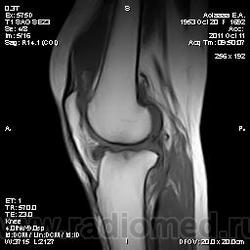

Дискуссия о природе "структры" в проекции передней поврехности метадиафиза бедренной кости.

Две версии: А. костно-хрящевой экзостоз. Б. разрастания сумки.

Пациента на МРТ прислали с травмой. "Это" было выявлено в ряду другой патологии как случайная находка. Рентген не было возможности сделать - дистанционная диагностика. Хотя это конечно была первая мысль. Спасибо за внимание к посту.

Если в демонстрации предполагается костно-хрящевой экзостоз, т.е. остеохондрома, то:

"Строение остеохондромы весьма характерно. Опухоль имеет грибовидную форму, ее размеры варьируют в пределах 1—20 см. Наружный слой головки этого новообразования покрыт различной толщины доброкачественным гиалиновым хрящом, хорошо видимым при МРТ. Хрящ имеет вид дезорганизованной ростовой пластинки. Он подвергается энхондральной оссификации, а вновь образованная кость формируется во внутренних частях головки и ножки. Корковый слой ножки опухоли сливается с аналогичным слоем диафиза кости, а костномозговые полости остеохондромы и самой кости сообщаются между собой."

Выделенная шрифтом фраза это ключевые отличительные дифференциально-диагностические признаки костно-хрящевого экзостоза от других поверхностных костных образований.

За надколенником по передней поверхности бедренной кости на МРТ и РКТ (наверное не так наглядно) - костно-хрящевой экзостоз.

tatyana, Вы в чем то правы. Складывается впечатление что кортикальная пластинка бедренной кости почти не изменена (или не изменена вовсе). Поэтому и были сомнения. Кроме того можно отметить, что вся синовиальная оболочка бурсы тотально утолщена, что тоже наводила на определенные соменения. Наверное изменение кортикальной пластинки, которые абсолютно четко увяжут заключение с костно-хрящевым экзостозом, можно указать с "натяжкой". Скорее это волевое решение в пользу костно-хрящевого экзостоза. Еще были мнения "вилонодулярном синовиите", а также "хондроматозе". Так что возможны варианты.